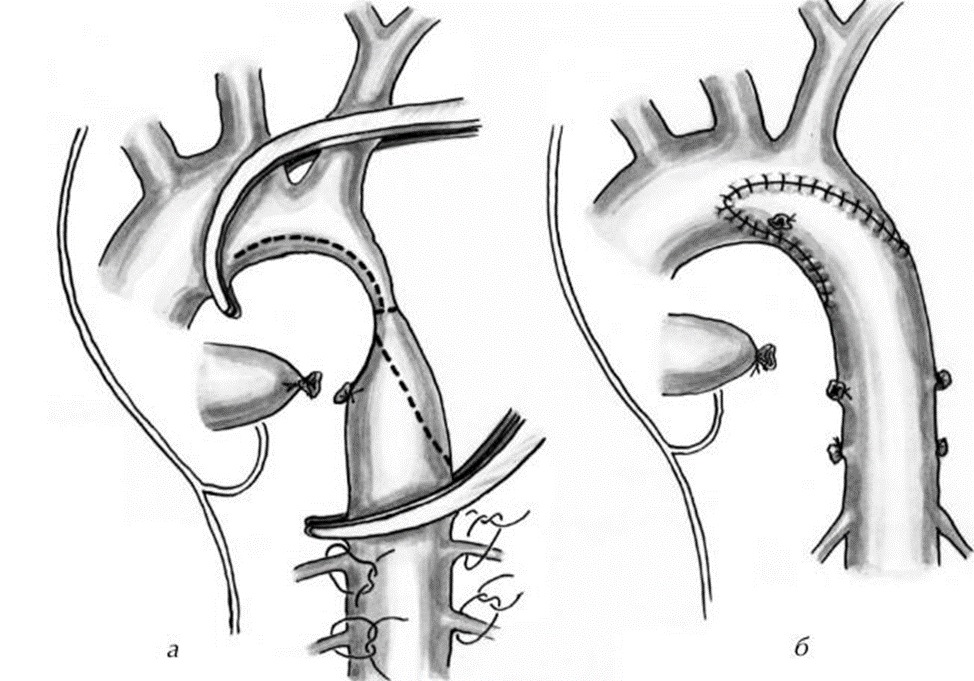

Впервые в Таразе 8-дневному новорожденному с критическим врожденным пороком сердца сделали экстренную операцию в Научно-клиническом центре кардиохирургии и трансплантологии (НКЦКТ) с диагнозом Критическая коарктация аорты. Новорожденный Г. в возрасте 8 дней, из города Тараз, поступил в НКЦКТ в крайне тяжелом состоянии, с жалобами на выраженную одышку в покое с ЧД 80 в минуту, синюшность кожных покровов, отсутствие мочи, сатурация кислорода 60%. Со слов мамы о пороке стало известно на втором триместре обследования УЗИ скрининг плода. В роддоме ОПЦ был выставлен предварительный диагноз ВПС Коарктация аорты. На 8 день жизни, учитывая критические жалобы обратились в городскую детскую больницу, оттуда направлен в НКЦКТ, где специалистами Центра проведено ЭХОКГ, КТ с контрастированием, диагноз подтвержден: Критическая коарктация аорты. Решением консилиума, в составе зав. детским кардиохирургическим отделением Мухамедовым Икромом, зав. реанимации Розбаевым Зафаром и детским кардиологом Уколовой Юлией, в 5 утра 8.10.2023 г. была выполнена по жизненным показаниям экстренная операция: резекция критической коарктации аорты с наложением протяженного анастомоза в «конец в конец».

Коарктация аорты представляет собой локализованное сужение просвета аорты, которое приводит к гипертензии в сосудах верхних конечностей. Может развиться молниеносная сердечная недостаточность и шок.